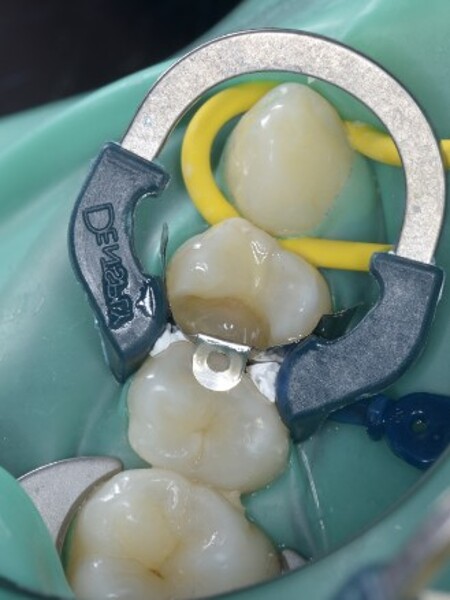

Predictable posterior restorations